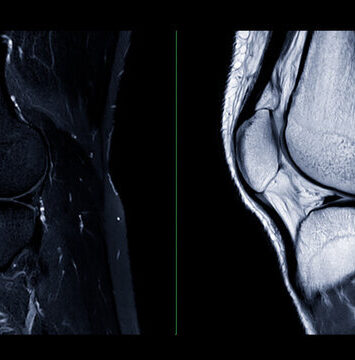

MRI of the Knee Joint Accurate Diagnosis for good Treatment

Knee joint MRI imaging is crucial for evaluating trauma, instability, or unexplained discomfort. It provides detailed...